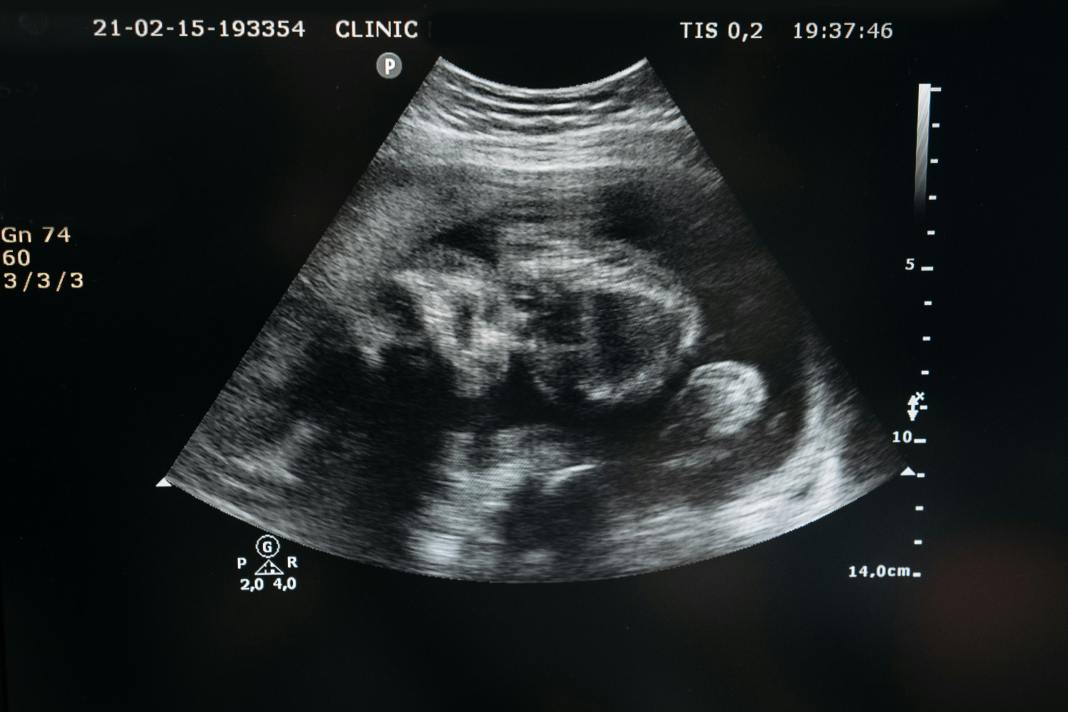

A remarkable medical breakthrough has occurred as doctors successfully performed fetal brain surgery on a baby girl near Boston. This pioneering operation, conducted in the womb, holds the potential to save lives and revolutionize the treatment of similar brain conditions in the future. The baby, diagnosed with vein of Galen malformation during a routine ultrasound scan, faced the risk of brain damage, heart problems, and breathing difficulties.